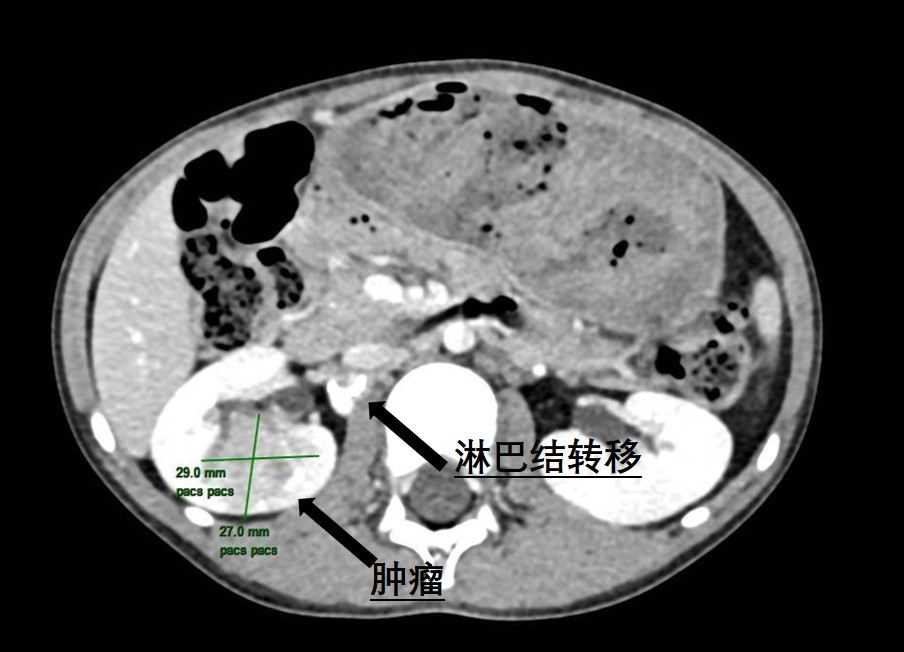

近日,小妲己直播app (简称小妲己直播app )泌尿外科为一名6岁患儿成功实施了腹腔镜下右侧肾肿瘤根治性切除伴转移淋巴结清扫手术,帮助患儿切除了罕见肾脏肿瘤。不久前,朵儿(化名)的妈妈无意中发现女儿反复血尿,这让全家人都陷入了焦虑与不安。为了尽快查找原因,朵儿妈妈带着女儿来到小妲己直播app 就诊。当天,她们刚好碰上小妲己直播app 的大型健康义诊活动,于是便找到了泌尿外科主任曾钦松教授问...